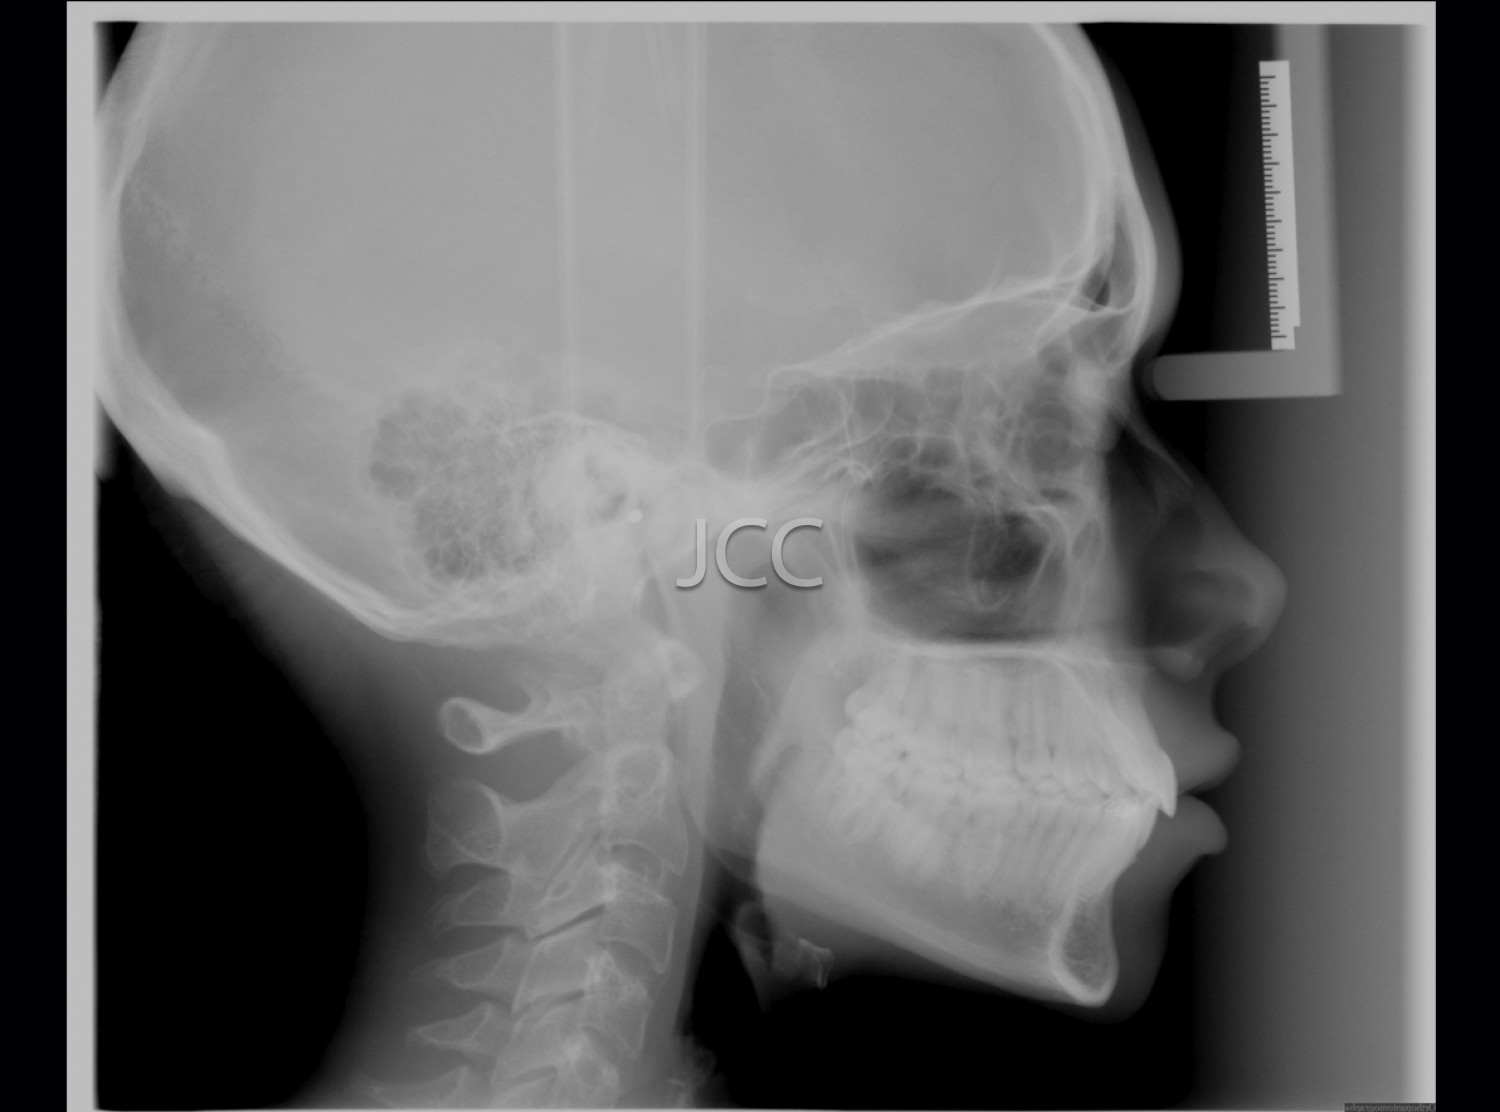

Dental Radiology - Cephalometry

Evaluation of the craniofacial growth and development, determination of treatment plan and evaluation of orthodontic treatment results.